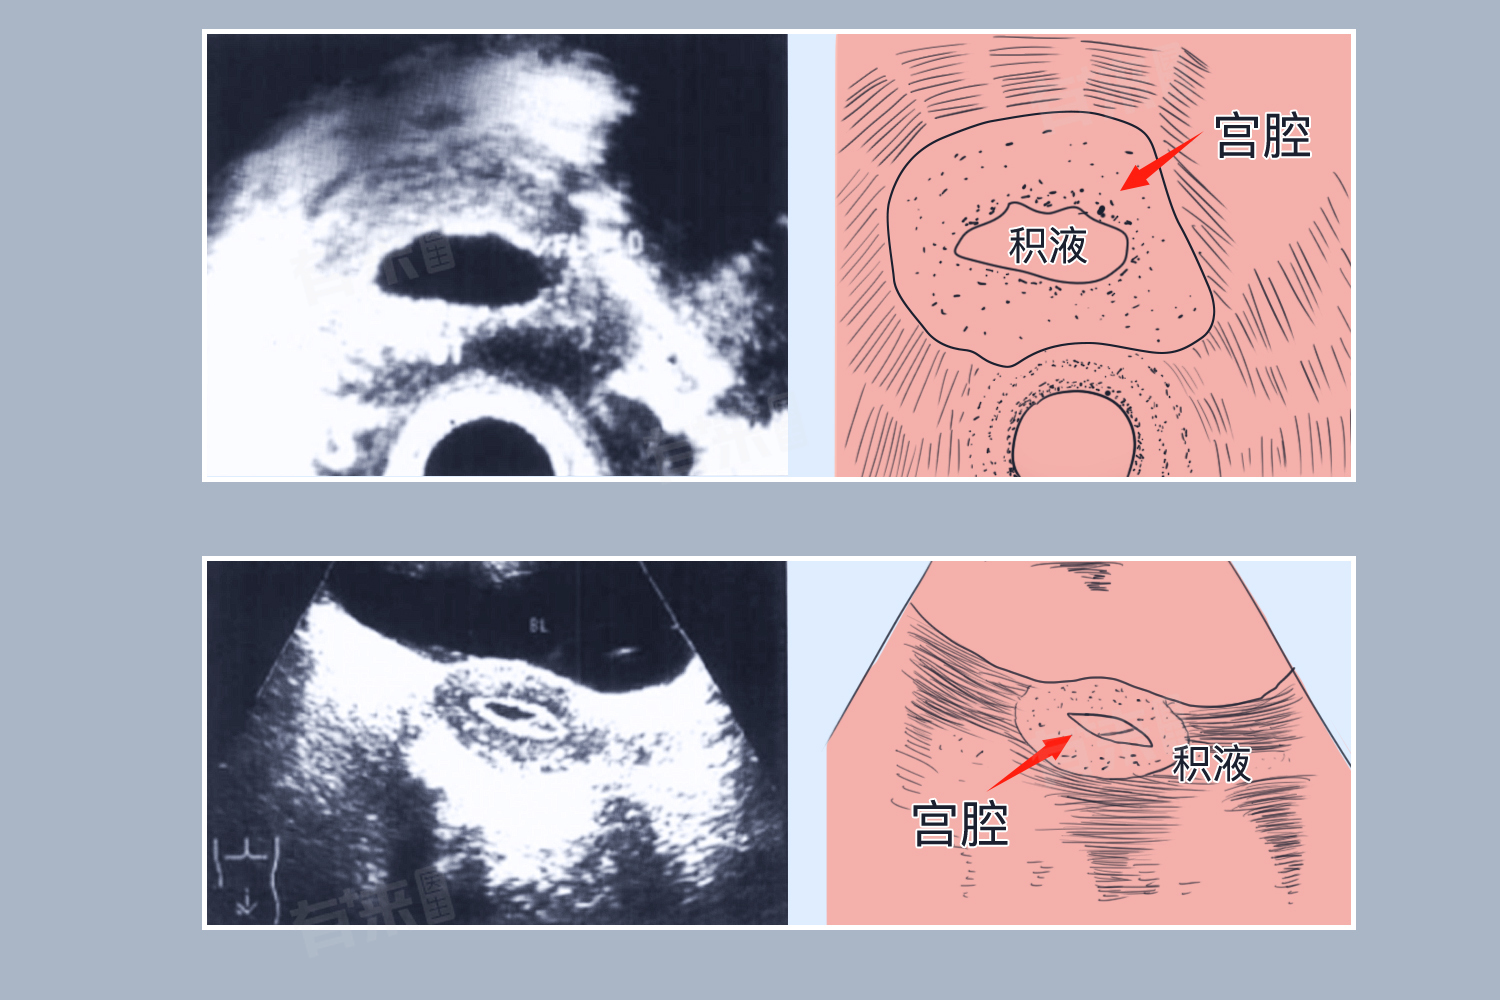

孕早期宫腔积液是指在怀孕初期,孕妇的子宫腔内出现了一定量的液体。孕早期宫腔积液的原因多种多样,包括生理性因素和病理性因素。生理性因素通常与激素变化、腹膜液堆积和子宫内膜增厚有关,而病理性因素则可能涉及内分泌失调、子宫内膜炎、先兆流产、异位妊娠等。

- 先兆流产:胚胎或母体的原因,如染色体异常、孕期感染等,可能导致先兆流产。此时,孕妇可能出现阴道出血、下腹疼痛等症状,并在B超中显示子宫腔内有积液。

- 异位妊娠:受精卵在子宫体腔以外的部位着床发育时,可能导致孕妇出现宫腔积液。这是因为受精卵的生长发育受限,无法形成正常的胎盘和羊水,使得宫腔内的液体无法正常排出。